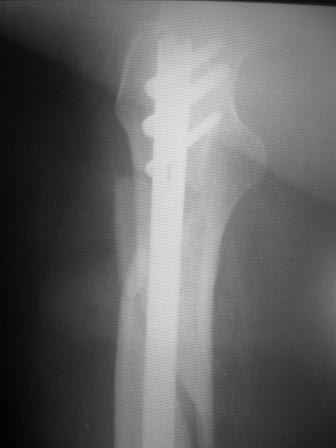

Пациент 83 года. Реконструктивный бедренный стержень Chm

коллеги в наличии есть только проксималный гвоздь chm длинна 260мм.отправить мы ее тоже никуда не можем т.к в облати внедряется тока у нас

Короткая версия 240 мм. Длинные начинаются с 260 мм? Попробуйте имеющуюся железку приложить к рентгенограмме - скорее всего, 260 мм будет маловато. Должна быть возможность связаться с поставщиком и поменять имеющийся гвоздь на аналогичный нужного размера.

Мда...не самый удачный случай для начинаний... Думаю, 260 мм здесь явно не подойдет(коротковат), перед разрезом добивайтесь максимально возможной репозиции на столе, определитесь с точкой введения штифта(это принципиальный момент), если физически этой точки не существует, то все равно вводите штифт через то место, где она должна была бы быть, постарайтесь вводить штифт ориентируясь по наружному кортикалу и ни в коем случае не идите диагонально. Сам клинок вводите под контролем в аксиальной проекции (естессно, сначала смотрим спицу в прямой). Удачи!)))

И еще: перед разрезом сориентируйтесь и отметьте маркером- ось дистального фрагмента (ориентир для ввода в него штифта), границы большого вертела. Важно ввести штифт в проксимальный фрагмент строго по его анатомическим ориентирам. Для этого устраните его смещения при помощи джойстиков или полуоткрытым способом (костодержателем) и в достигнутом положении вводите штифт.